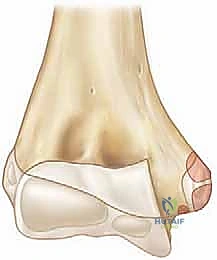

For pediatric and adolescent patients, a thorough understanding of the radiographic appearance of the secondary ossification centers is crucial. The mnemonic CRITOE (Capitellum, Radial head, Internal/medial epicondyle, Trochlea, Olecranon, External/lateral epicondyle) dictates the chronological order of appearance. The medial epicondyle typically ossifies between ages 4 and 6 and fuses to the distal humeral shaft between ages 15 and 18. Because the apophysis is largely cartilaginous in younger patients, plain radiographs may grossly underestimate the true size of the avulsed fragment and the extent of the soft-tissue disruption. Furthermore, the surgeon must be acutely aware of the olecranon fossa, located immediately posterior and lateral to the medial epicondyle. Any hardware traversing the epicondyle must be directed anteriorly to avoid breaching the fossa, which would result in a catastrophic mechanical block to terminal elbow extension.

Once anatomical reduction is achieved, it is provisionally stabilized using 1.6 mm or 2.0 mm Kirschner wires (K-wires) or the guide pins from a cannulated screw system. The trajectory of these pins is absolutely critical. The starting point is on the anterior-inferior aspect of the medial epicondyle. The pins are directed superiorly, laterally, and anteriorly into the distal humeral metaphysis.

Directing the pins anteriorly is paramount to avoid penetrating the olecranon fossa. A second pin is highly recommended to provide rotational stability during the subsequent drilling and tapping phases. Following pin placement, the reduction and pin trajectory are rigorously evaluated using orthogonal AP and lateral fluoroscopy. The elbow is taken through a gentle range of motion under live fluoroscopy to confirm that the hardware does not impinge on the joint and that the reduction remains stable under dynamic stress.

For definitive fixation, a 4.0 mm or 4.5 mm partially threaded cannulated screw is the gold standard. The appropriate screw length is determined using a depth gauge over the primary guide pin. The lateral cortex of the humerus should ideally be engaged to maximize pull-out strength, particularly in older patients or those with osteopenic bone.

The outer cortex of the epicondyle is overdrilled to create a gliding hole, facilitating interfragmentary compression. The screw is then advanced over the guide wire. If the epicondylar fragment is comminuted or if the patient is very young with a soft, cartilaginous apophysis, a spiked ligament washer or a standard low-profile washer should be utilized to distribute the compressive forces and prevent the screw head from burying into the fragment.

Once the primary screw is seated and excellent compression is achieved, the secondary anti-rotation K-wire is typically removed, unless the fragment is highly unstable, in which case it may be exchanged for a smaller secondary screw. Final fluoroscopic images are obtained to verify anatomical reduction, appropriate hardware length, and clearance of the olecranon fossa. The ulnar nerve is inspected one final time to ensure it is free from tension or hardware impingement before the wound is closed in layers.